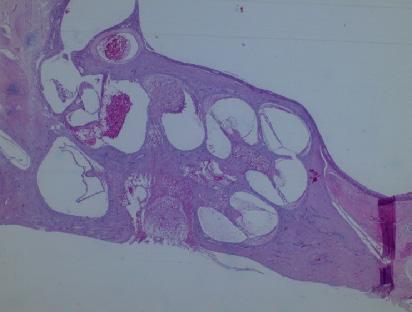

Intervențiile chirurgicale care se efectuează sunt la nivelul celor mai înalte standarde de performanță în toate domeniile chirurgiei otologice, începând cu chirurgia sechelelor simple postotitice (miringoplastia, tim-panoplastia); chirurgia otosclerozei (Fig. 1), continuând cu chirurgia colesteatomului și a tumorilor urechii. Colesteatomul, care este o pseudotumoră inflamatorie, rămâne una dintre cele mai distructive boli ale urechii medii, care poate cauza uneori complicații amenințătoare de viață. Dacă în trecut

tehnicile chirurgicale erau cele radicale, la ora actuală pe lângă eradicarea bolii prin chirurgie se urmărește și reconstrucția mecanismului auditiv prin proteze pasive de ureche medie, cele mai folosite fiind cele din titan. (Fig. 2). Fiecare pacient este evaluat iar tratamentul este aplicat individualizat în funcție de caracteristicile patologiei. Reabilitarea auditivă este personalizată și în cazurile în care nu se pot realiza prin proteze pasive, utilizându se noile dispozitive moderne, precum implantele cu transmisie osoasă (BAHA, BONEBRIDGE, OSSIA) (Fig. 3) care oferă soluții în cazul pacienților, care în trecut nu aveau speranțe terapeutice. Pe lângă munca cu pacienții, cercetarea clinică reprezintă un loc important în disciplina noastră. Studiile științifice se referă la analizarea rezultatelor tratamentului chirurgical, dar și studii de calitate a vieții pacienților cu otite medii supurate cronice. La acestea se adaugă studiile referitoare la etiopatogeneza bolilor inflamatorii cronice ale urechii medii, în ceea ce privește factorii anatomici precum și unii biomarkeri moleculari implicați. Antrenamentul chirurgical al rezidenților și specialiștilor este un domeniu important în activitatea noastră. Astfel, anual se organizează cursuri de speci-alizare postuniversitare (audiologie, chirurgia surdității și screening auditiv). (Fig. 4) În domeniul patologiei urechii interne se cunoaște faptul că distrugerea celulelor neurosenzoriale din cohlee este ireversibilă la om, iar surditatea neurosenzorială rămâne definitivă. Implantul cohlear este un dispozitiv performant care a schimbat perspectiva copiilor născuți surzi, prin implantare cohleară aceștia fiind capabili să urmeze o școală normală. De asemenea, persoanele suferinde de hipoacuzie profundă își pot recăpăta auzul cu creș-

Fig.1 Imagine intraoperatorie. Otoscleroză-se vede plasarea protezei de titan în fereastra ovală-corectarea auzului pacientului

Fig. 2 Imagine intraoperatorie. Colesteatom-refacerea mecanismului auditiv cu proteză parțială din titan

Fig. 4 Antrenament chirurgical în laboratorul de disecție

Fig. 3 Proteză BAHA pentru recuperarea auditivă

Fig. 5 Copil implantat auditiv pentru recuperarea auzului

Fig. 8 Organul corti-prelevat de la animale-imagine de microscopie electronică

Fig. 9 Imagine de microscopie elecronică-se văd nanoparticulele de AgNO3 pătrunse în celulele de ureche internă recoltate de la animale viabile în culturi celulare

Fig.10 Imagine de microscopie elecronică-se văd nanoparticulele de AgNO3 pătrunse în celulele de ureche internă recoltate de la animale viabile în culturi celulare

Fig. 6 Electrod intracohlear după implantare cohleară-imagine computer tomografică

Fig. 7 Secțiune prin cohleea recoltată de la animale